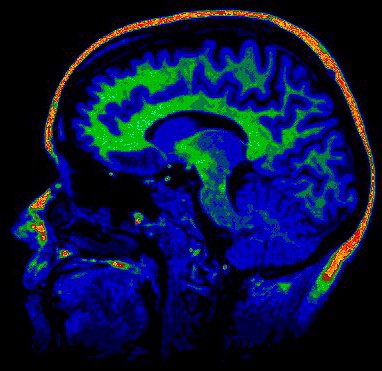

L’activité cérébrale, comme l’ont illustré les IRM, est un feux d’artifice permanent, elle est provoquée par d‘infimes décharges électriques qui parcourent notre cerveau à la vitesse de la lumière ; différentes zones du cortex s’activent, s’animent et s’illuminent ; elles correspondent entre elles et forment des nuages de pensée, coordonnent nos actions, reçoivent des émotions et des sensations… Pouvons nous devenir des êtres plus subtils et éviter la fascination mortifère pour un Super Ordinateur Central (Hall dans 2001 l’Odyssée de l’espace de Stanley Kubrick en 1968) qui viderai nos batteries d’énergies vitales jusqu’à la dernière goutte (Dark Cristal de Jim Henson et Frank Oz en 1982, Matrix par les frères Andy et Larry Wachowski en 1999) nous transformant en ectoplasmes cybernétiques ?…